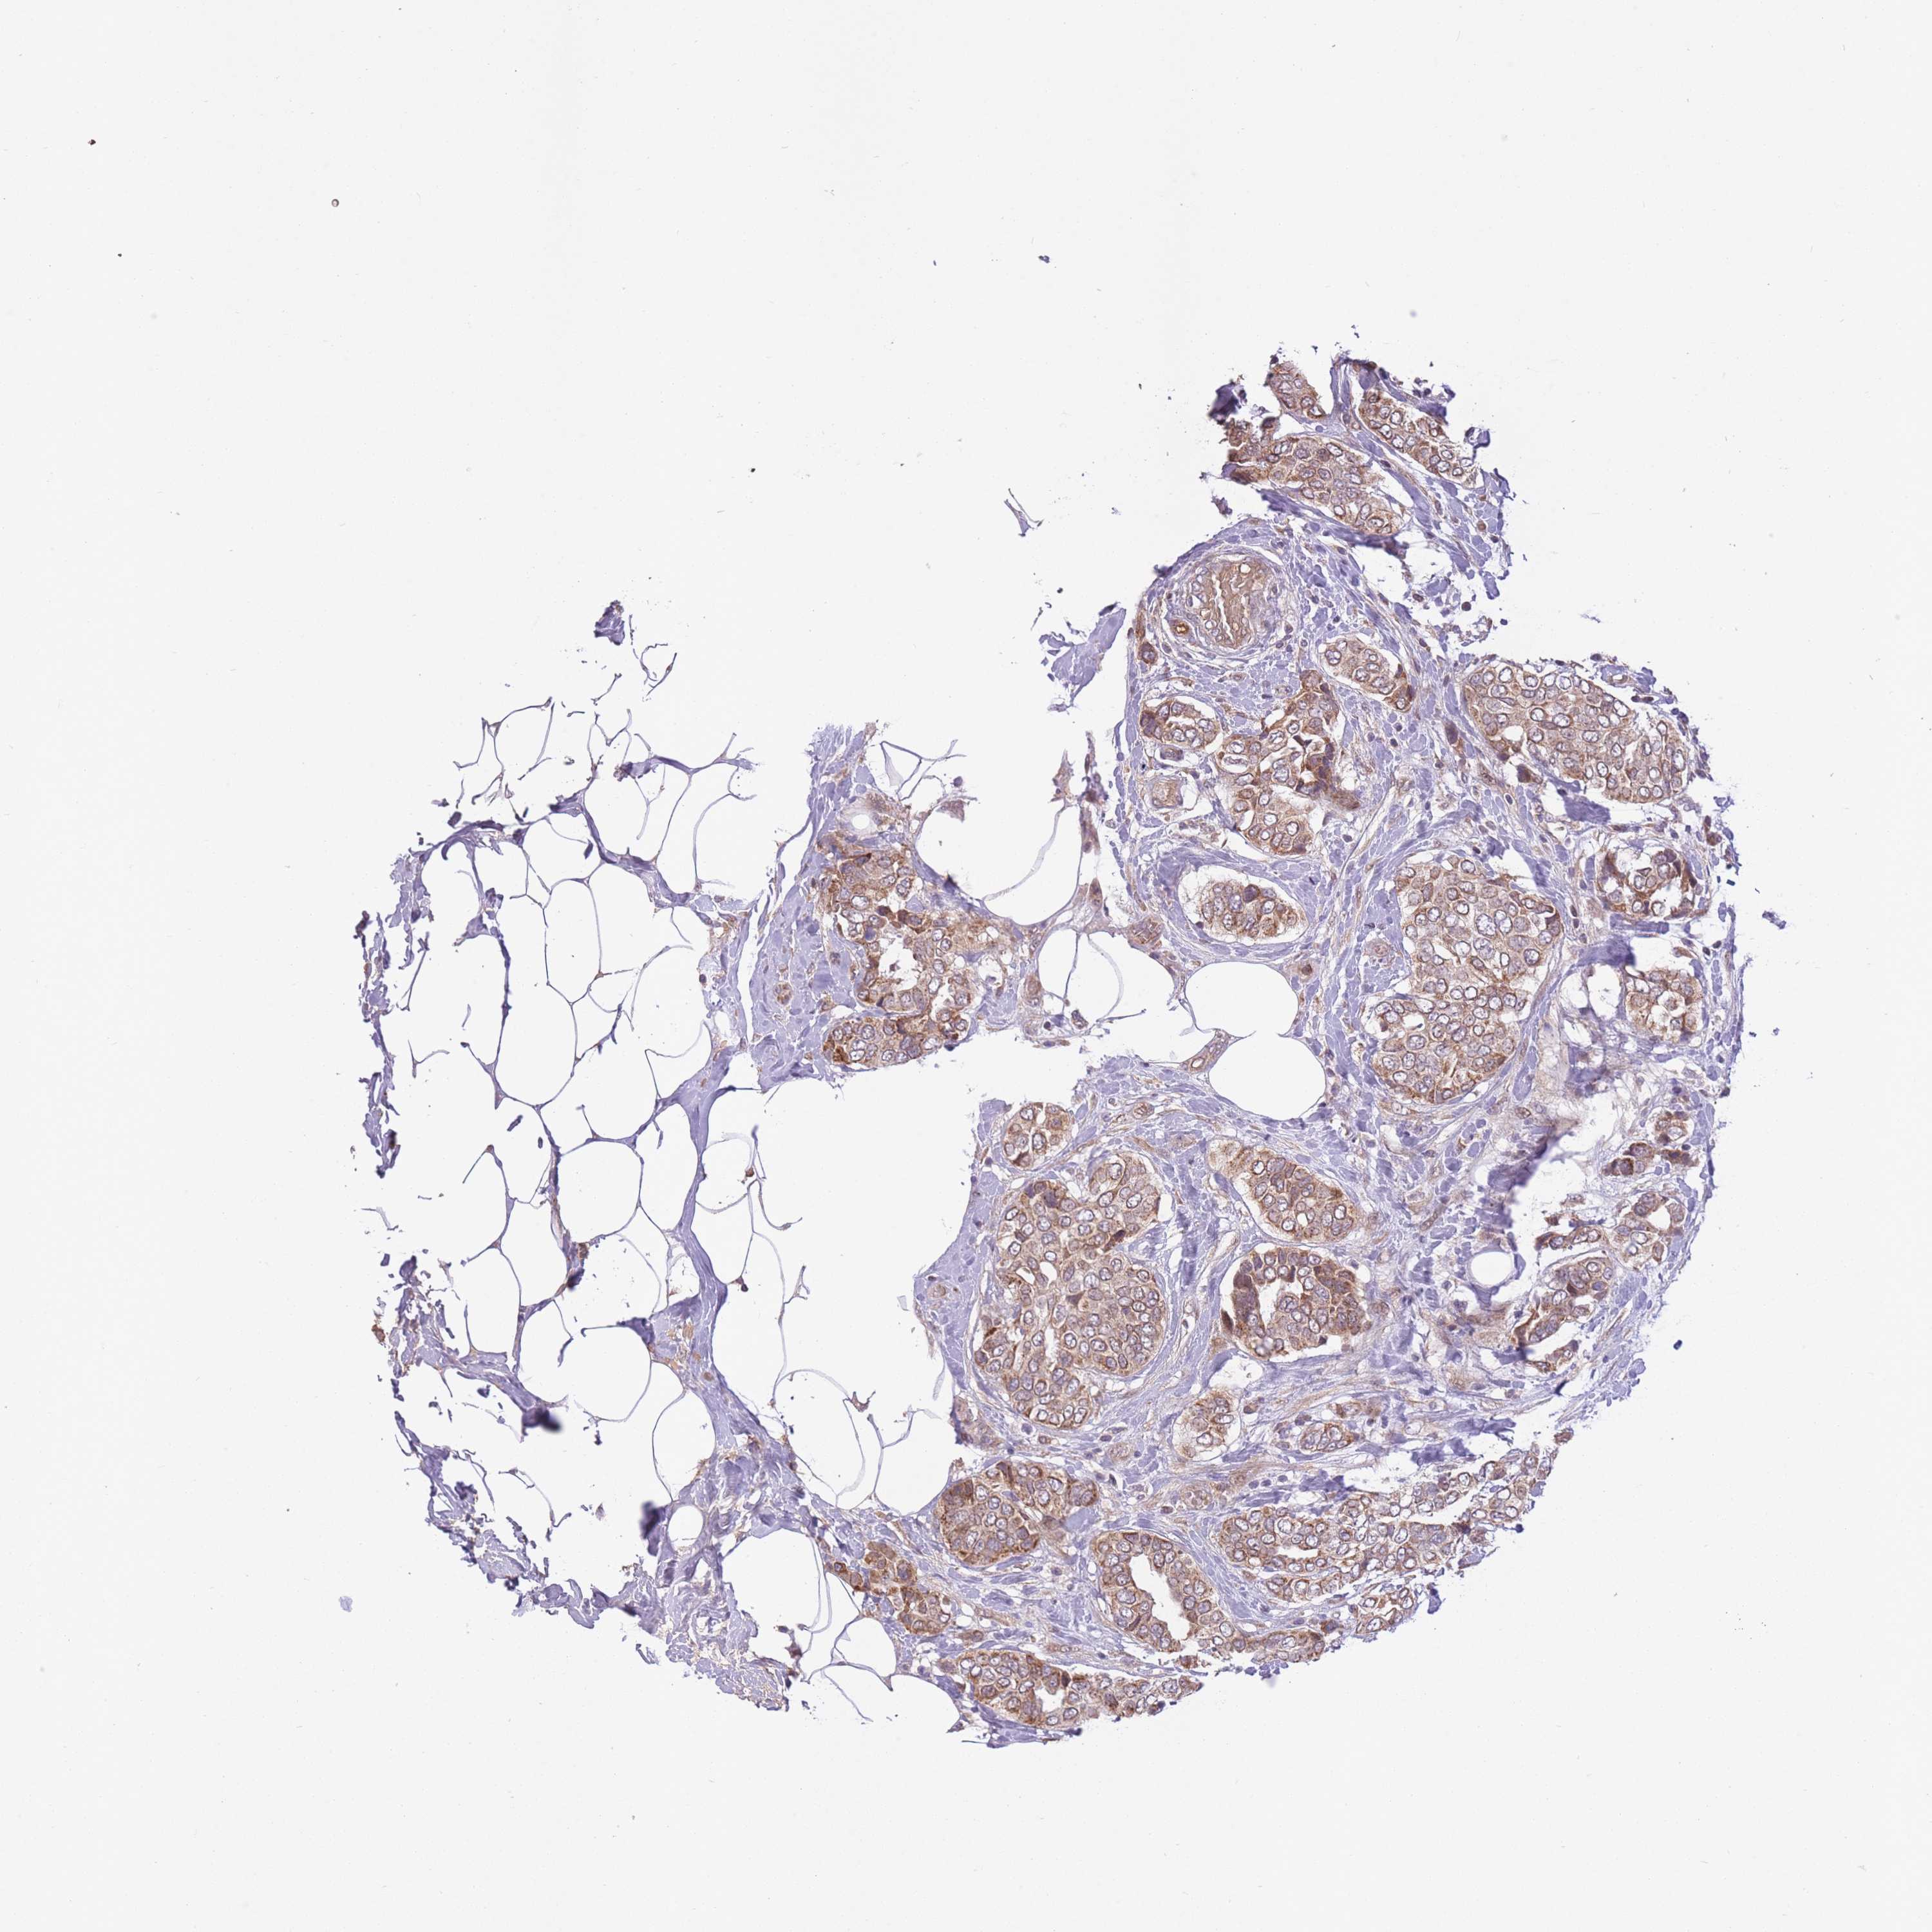

CANCER BREAST CANCER Show tissue menu

BRCA TCGA BRCA VALIDATION PROTEIN EXPRESSION

Breast cancer

Human cancer